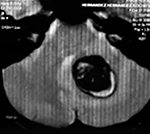

EJEMPLO DE CASO CLÍNICO (8)

Paciente femenino de 29 años de edad con historial de cefalea crónica que presenta súbitamente disdiadococinesia y dismetría izquierda.

El estudio de RMN presenta una lesión bien circunscrita en hemisferio cerebeloso izquierdo con periferia de predominio hiperintenso en T1 y T2, y centro hipointenso, edema perilesional mínimo, así como una imagen de un vaso venoso alimentador que recorre hacia el ángulo pontocerebeloso izquierdo.

Se realizó una craniectomía suboccipital paramedial derecha, así como un abordaje transcortical en el hemisferio cerebeloso izquierdo llegando a la región perilesional de aspecto amarillento, posteriormente se observa una lesión oscuro-verdoso de contenido hemático antiguo, retirando la cápsula y su contenido en la totalidad.

La evolución clínica de la paciente fue satisfactoria solo preservando la dismetría como secuela.

El resultado histopatológico fue consistente en angioma cavernoso.

El estudio de control de RMN se observa la brecha quirúrgica y ausencia de lesión (figs. 1, 2 y 3).

Figura 2:

Cortes axiales en ponderación T1, cambios postquirúrgicos.